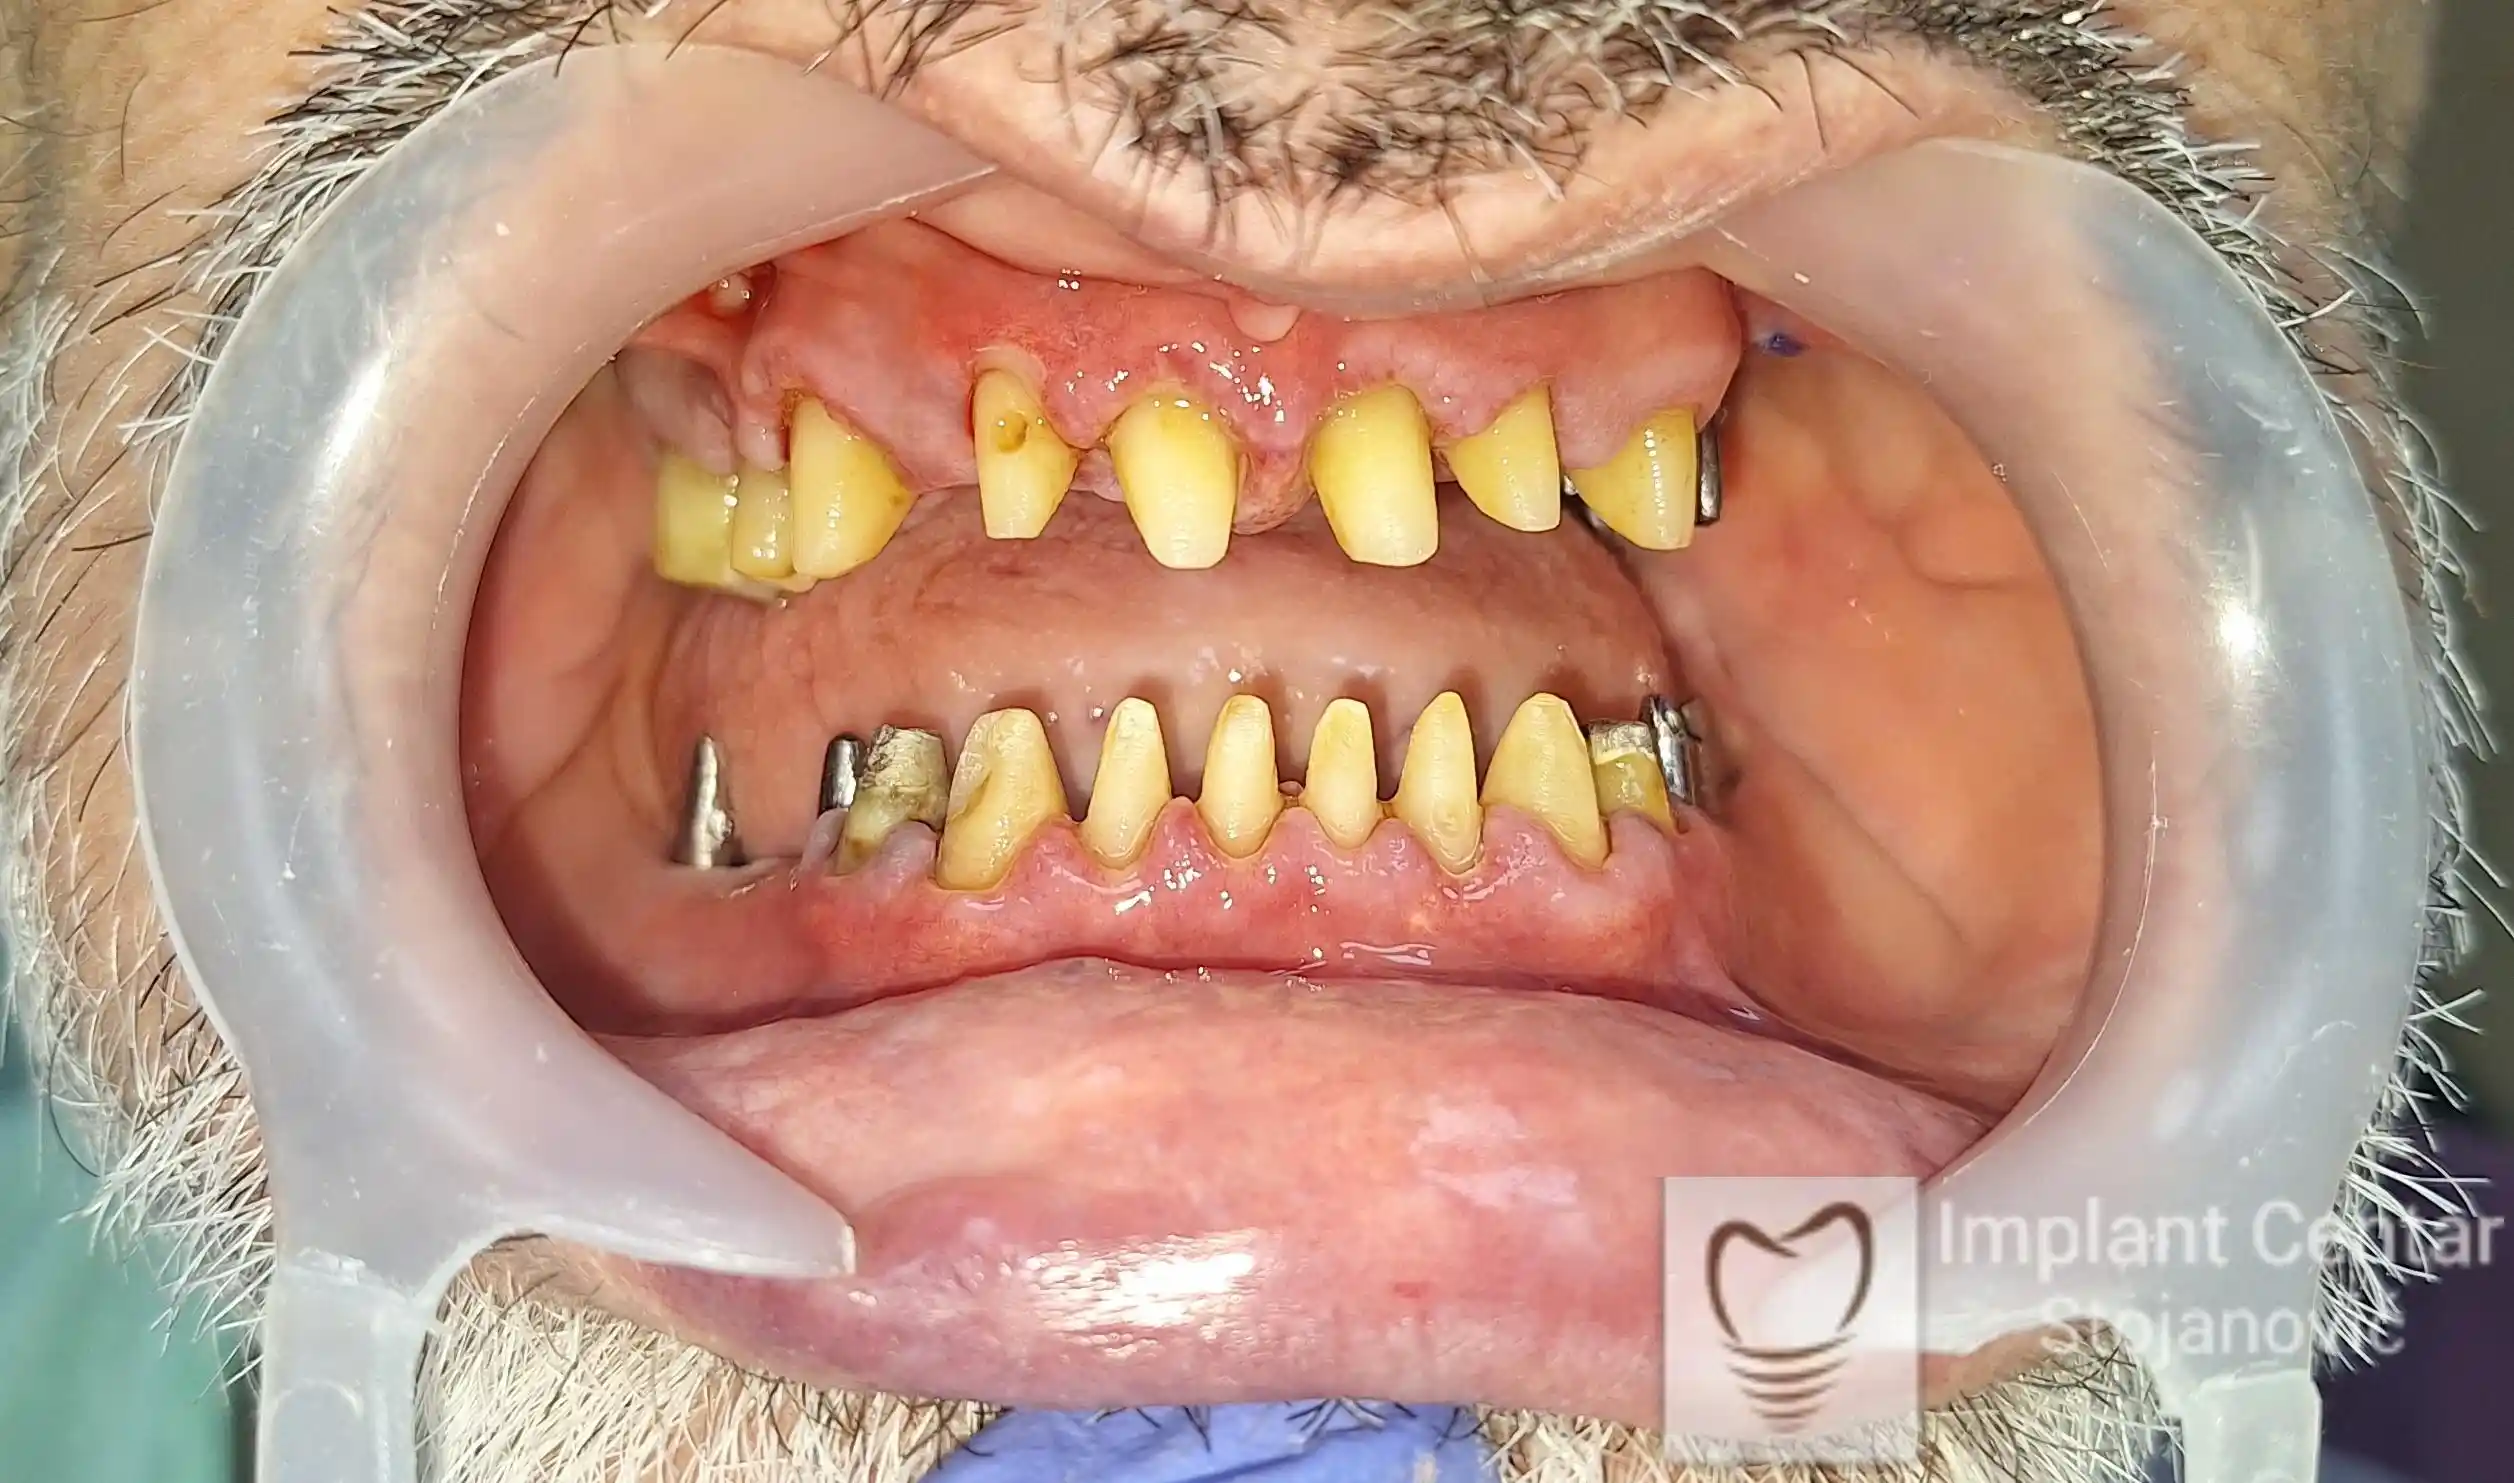

Na slikama 1, 2, 3 , 4  i  5 prikazan je izgled pacijenta pre početka terapije. Nakon detaljne kliničke i radiološke analize, doneta je odluka o vađenju zuba loše biološke vrednosti, dok su bezuba polja sanirana ugradnjom dentalnih implantata.

Nakon ugradnje implantata i pripreme preostalih zuba, pacijentu su izrađene fiksne privremene krunice, čime je postignut eugnatan zagriz već nakon jednog dana (slika 8, 9 i 10). Tokom perioda osteointegracije, pacijent se postepeno privikavao na novi položaj vilica i zagriz.

Po završetku perioda integracije, izrađeni su definitivni cirkonijum-keramički mostovi, čime je postignuta potpuna rekonstrukcija zagriza, kao i značajno poboljšanje estetike i oralne funkcije (slika 12, 13, 14 i 15).